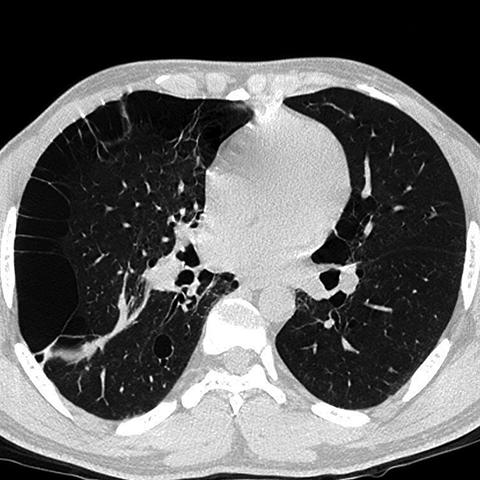

Paraseptal Emphysema & Bullous Disease [2 of 2]